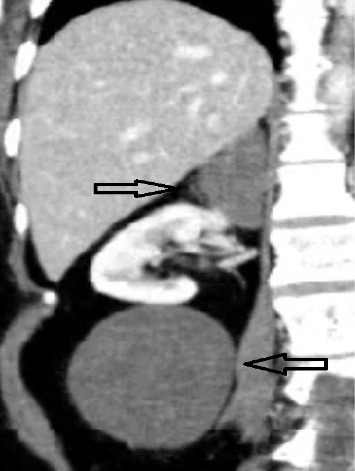

这个病例报告了一个罕见的同步肾上腺神经节神经瘤和同侧腹膜后肿块的51岁女性发作性高血压危象和增加的症状频率。影像显示右肾附近有一个低密度肿块和一个额外的肾上腺肿块,导致手术干预。实验室结果显示高皮质醇,两个肿块通过腹腔镜手术切除。术后病理证实两个肿块为成熟型神经节神经瘤,无恶性征象或并发症。本病例强调了这种罕见表现的诊断和治疗挑战,并强调了详细成像,手术切除和组织病理学分析的重要性。正如本文所观察到的,皮质醇水平升高与神经节神经瘤之间的潜在联系强调了对这些良性肿瘤进行进一步研究的必要性。

This case report presents a rare instance of synchronous adrenal ganglioneuroma and an ipsilateral retroperitoneal mass in a 51-year-old woman with episodic hypertensive crises and increased symptom frequency. Imaging revealed a hypodense mass near the right kidney and an additional adrenal mass, which led to surgical intervention. Laboratory findings indicated hypercortisolism, and both masses were surgically removed by the laparoscopy approach. Postoperative pathology identified both masses as maturing-type ganglioneuroma, with no signs of malignancy or complications. This case highlights the diagnostic and therapeutic challenges of such rare presentations and emphasizes the importance of detailed imaging, surgical excision, and histopathological analysis. The potential link between elevated cortisol levels and ganglioneuroma, as observed here, underscores the need for further research into these benign tumors.